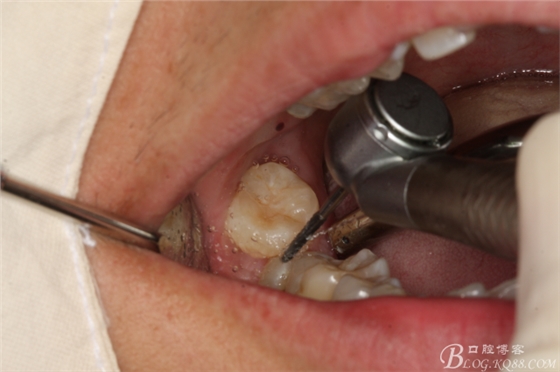

圖7.不切開、不翻瓣、利用有限空間直接高速牙鉆分牙

圖8.先橫斷47牙冠,盡量從牙頸部橫斷